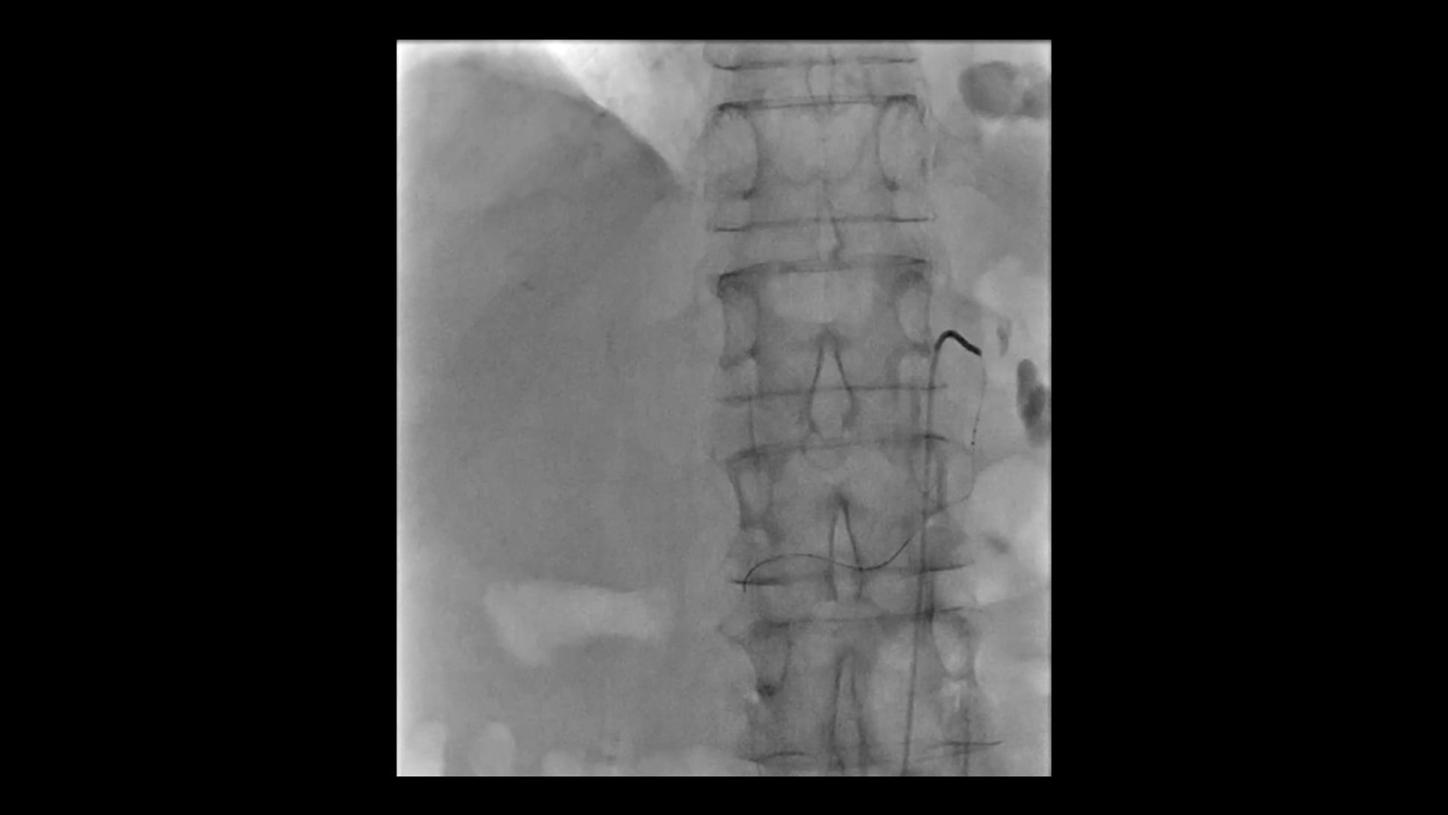

Future-focused IR imaging for a broad procedure mix

Discover how leading clinicians are transforming interventional radiology with Siemens Healthineers technologies. From ultra-fast 3D imaging to laser-guided needle procedures, the ARTIS icono ceiling powered by OPTIQ and syngo DynaCT are redefining what’s possible in IR. Explore real-world cases, expert insights, and the future of image-guided therapy.